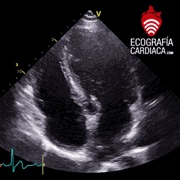

APICAL 4 CH*